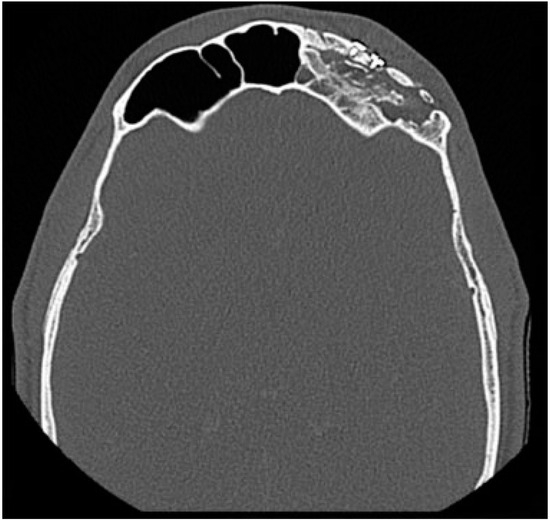

Fractures isolated to the posterior table are rarely observed (1–7%)[16,30,31] and are more common in younger patients. Typically, the posterior table is fractured in conjunction with injuries to the anterior table and FSOT (Figure 5). The sinus septae may transmit some of the anterior force to the posterior wall, or there may be direct posterior wall disruption.

Figure 5. (a) CT in the sagittal plane demonstrating a displaced, comminuted fracture of the posterior table. There are also associated fractures of the anterior skull base along with obstruction of the FSOT with bony fragments. (b) CT in the coronal plane of the same fracture.